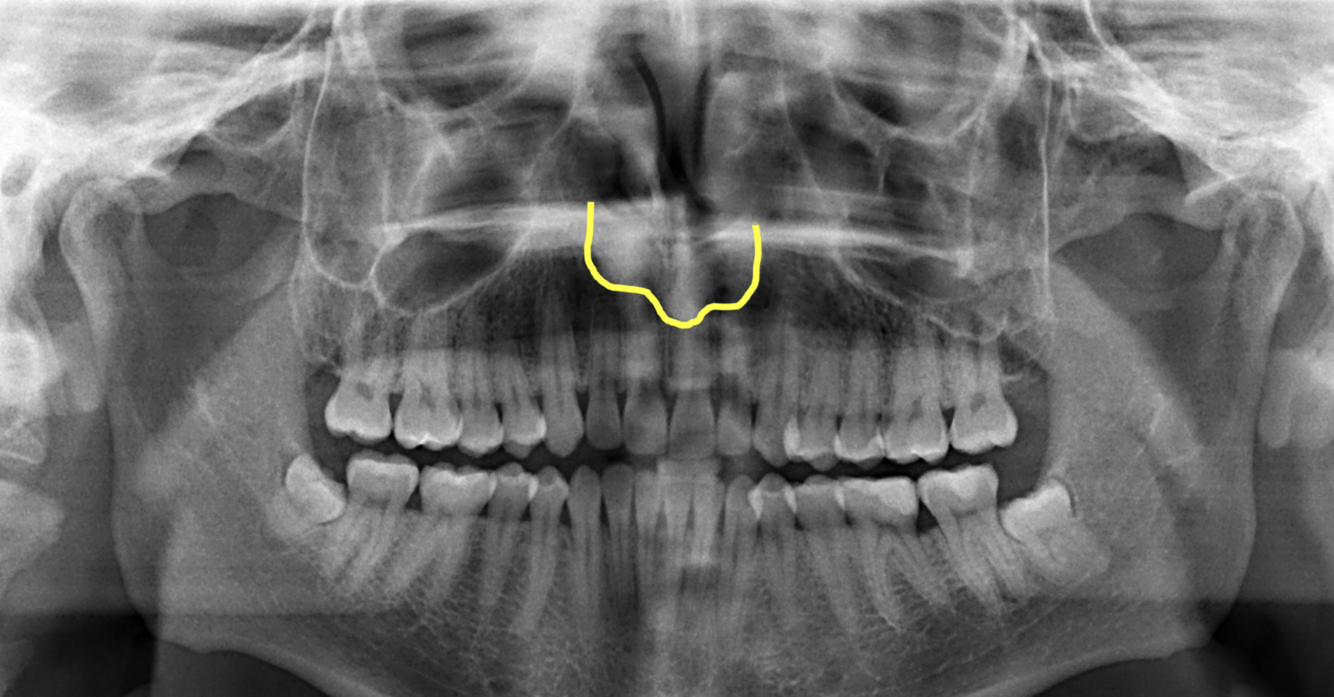

What does the orange indicate in the following image?

Intermaxillary suture